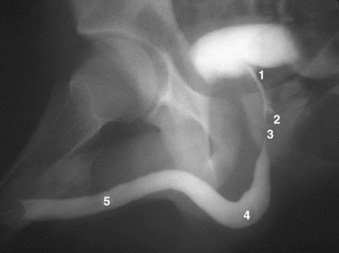

Figure 2–37 Retrograde urethrogram of the male urethra demonstrating urethral anatomy. 1, prostatic urethra; 2, verumontanum, into which enter the ejaculatory ducts; 3, membranous urethra, note physiologic narrowing of urethral luminal diameter due to external striated sphincter; 4, bulbar urethra; 5, pendulous urethra.

Beyond to the urethral angle, all major glandular elements of the prostate open into the prostatic urethra. The urethral crest widens and protrudes from the posterior wall as the verumontanum (see Figs. 2-35, 2-37, and 2-38). The small slitlike orifice of the prostatic utricle is found at the apex of the verumontanum and may be visualized cystoscopically. The utricle is a 6-mm müllerian remnant in the form of a small sac that projects upward and backward into the substance of the prostate. In males with ambiguous genitalia, it may form a large diverticulum that protrudes from the posterior side of the prostate. To either side of the utricular orifice, the two small openings of the ejaculatory ducts may be found. The ejaculatory ducts form at the juncture of the vas deferens and seminal vesicles and enter the prostate base, where it fuses with the bladder. They course nearly 2 cm through the prostate in line with the distal prostatic urethra and are surrounded by circular smooth muscle (see Fig. 2–36; see also Figs. 2-27 and 2-31).